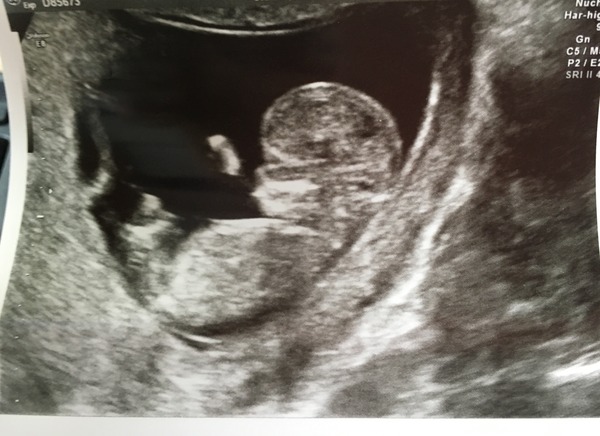

Feeling very happy after my scan! Puts me at 12+4 do due date moved to the 1st.

Great photo balalala Smile

Great photo baggy! So pleased it went well with you too! Since getting home I've become obsessed with the nub theory... Is the thing I can see in the scan the umbilical cord?

It's a waving arm! Oh yes, someone was telling me about that the other day but I said as we're not finding out I don't want to know, so I can't guess! I wouldn't be surprised if it's another DS though, as boys just run in the family in both sides! Twins also run in the family, so I was relieved to see just the one!

Lovely scan photo bala!

Great scan photo Bala!